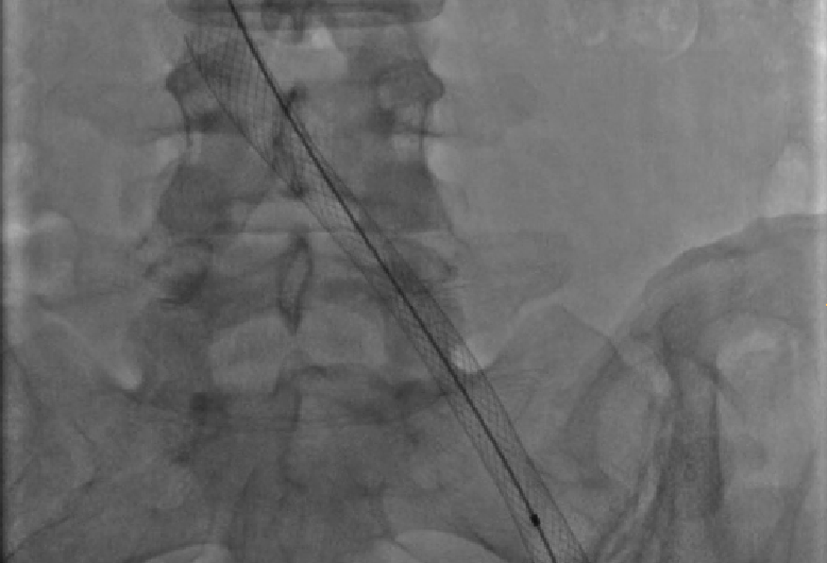

Elevata specializzazione nel trattamento della patologia arteriosa ostruttiva e aneurismatica (carotidi, aorta, arti inferiori) sia con tecnica di chirurgia aperta che endovascolare.

Leader mondiali nella chirurgia ricostruttiva del sistema venoso profondo, nel trattamento endovascolare della trombosi venosa acuta e della patologia ostruttiva cronica.